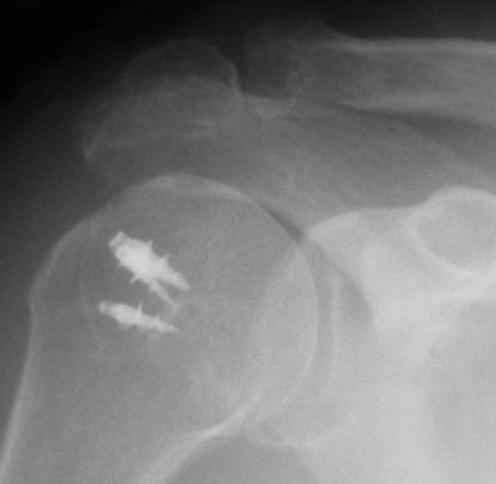

Верхний подвывих в такой ситуации может быть проявлением ротаторной артропатии, как следствия более массивного, чем частичный разрыв сухожилия надостной мыщцы, повреждения вращательной манжеты. И значит нужно думать о том, насколько полно восстановлена манжета, адекватно ли был расценен объем ее повреждения. Что за шов применялся? Якорных винтов не видно. И почему гипсовая иммобилизация? Есть прекрасные надувные отводящие подушки, позволяющие ранние движения.

В качестве примера - снимки до и после восстановления целостности вращательной манжеты после 3-хмесячной давности полного разрыва. Видно, что верхний подвывих устранен.

Шов сухожилия надостной мышцы чаще всего оказывается неэффективным из-за разволокненной дистальной части(что является причиной повреждения).Полностью согласен с мнением о сохраняющемся большом дефекте. В этом случае с диагностикой помогает УЗИ, МРТ. Если решите оперировать, может помочь небольшой предоперационный курс проводниковых наключичных блокад (№6 на 2 недели, без адреналина) с попыткой постепенной редрессации сустава. Движения могут и не восстановиться, а кровоток в этой зоне точно улучшите. Даже в свежих случаях наиболее эффективна реинсерция ротаторов(выше отличный пример с анкерами). Бюджетный вариант - это привязать нити от прошитых сухожилий к головке винта, введенного на 2-4 см. ниже верхушки б\бугорка. Затем отводящая шина не менее 6 недель.